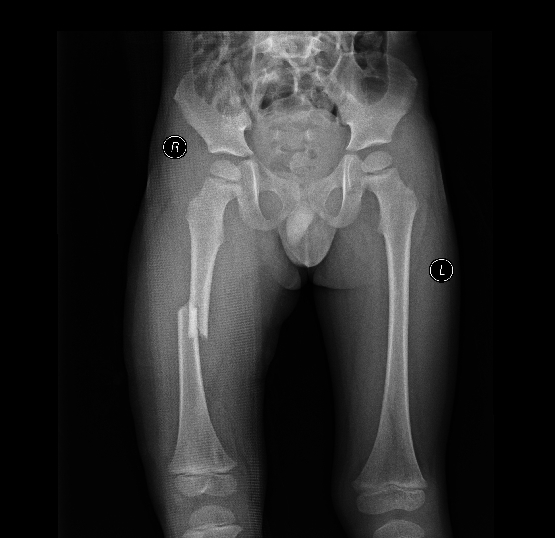

3月女婴股骨骨折正位片

3月女婴股骨骨折侧位片

2 月后复查正位片

2月后复查侧位片

1年后复查正位片,已完全愈合,自行矫形至正常